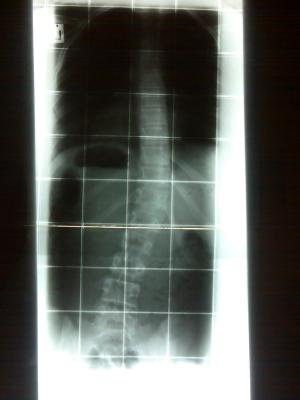

hab jetzt mal ein röntgenbild von meiner ws hochgeladen. bilder von meinem korsett werde ich wahrscheinlich dann nur bei der korsett-modenschau hochladen.

von hinten

forum_photo.jpg (12.05 KiB) 8444 mal betrachtet